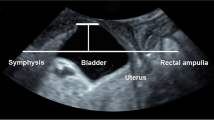

A cross-sectional observational study was performed, enrolling consecutive women seeking cares for lower urinary tract symptoms (LUTS) with evidence of POP. Data regarding baseline characteristics, LUTS, and physical examination were gathered for each patient. Multivariate analysis (multiple linear regression (MLR)) and artificial neural networks (ANNs) were performed to design predicting models.